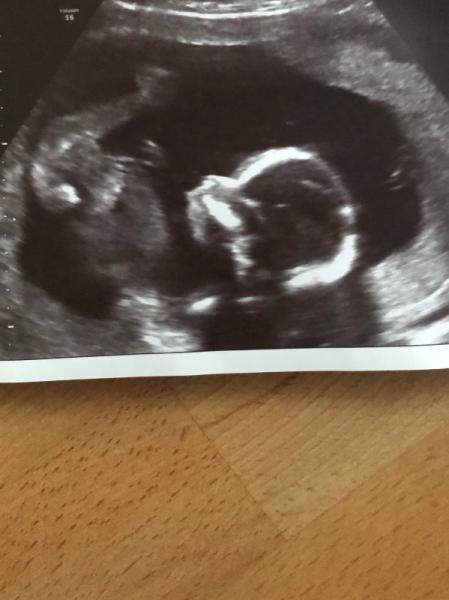

was seht ihr?

Bild zu rosa oder hellblau - Forum für Juni - Mamis

Aus der Perspektive kann man das Geschlecht nicht erkennen. Aber schöne Aufnahme im Profil.

Würd ich so nicht unbedingt sagen. Bei meinem Sohn sah man aus dieser Perspektive die Hoden. Was hier nicht der Fall ist. Was jetzt aber auch nicht 100% auf ein Mädchen hindeutet

meine ärztin meinte eher mädchen, möchte aber kein gewicht auf diese aussage geben. ich persönlich habe auch das gefühl schamlippen zu sehen. die beine sind ja weit offen naja, bleibt wohl spannend.

ich sage Mädchen, da die Stirn runder ist..

Ich denke Mädchen. Weil wenn es ein Junge wäre würde man das schon in der 18 Ssw sehen. Bei mir hat man es in der 13 Ssw deutlich gesehen dass es ein Junge ist und es ist auch dabei geblieben.